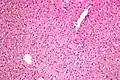

In liver pathology, a ground glass hepatocyte, abbreviated GGH, is a liver parenchymal cell with a flat hazy and uniformly dull appearing cytoplasm on light microscopy. The cytoplasm's granular homogeneous eosinophilic staining is caused by the presence of HBsAg.

The appearance is classically associated with abundant hepatitis B antigen in the endoplasmic reticulum, but may also be drug-induced.[1][2] In the context of hepatitis B, GGHs are only seen in chronic infections, i.e. they are not seen in acute hepatitis B.

Micrograph showing ground glass hepatocytes. H&E stain. -